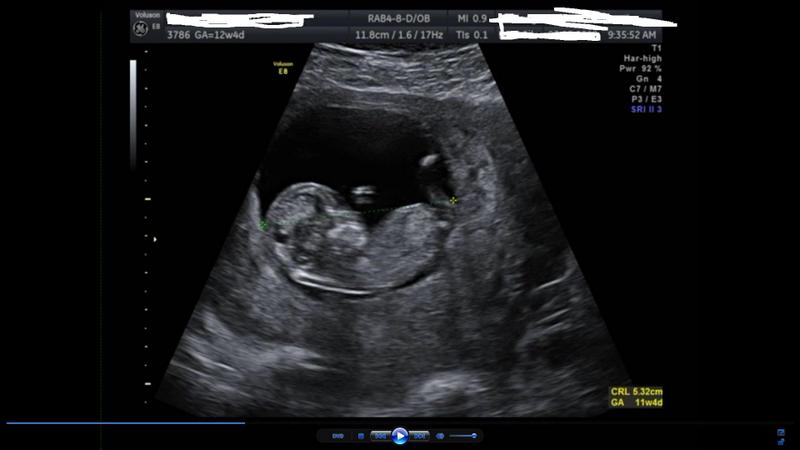

Had my 12w4d ultrasound last friday. Here is the picture - not much to go on though. I asked the sonographer about gender and he was a real arse, so think he went nowhere near the nub on purpose! Anyway, guess away just for fun.

I tried to take some screen shots from the video, but they come out way too big to post here.

Attachment 2858